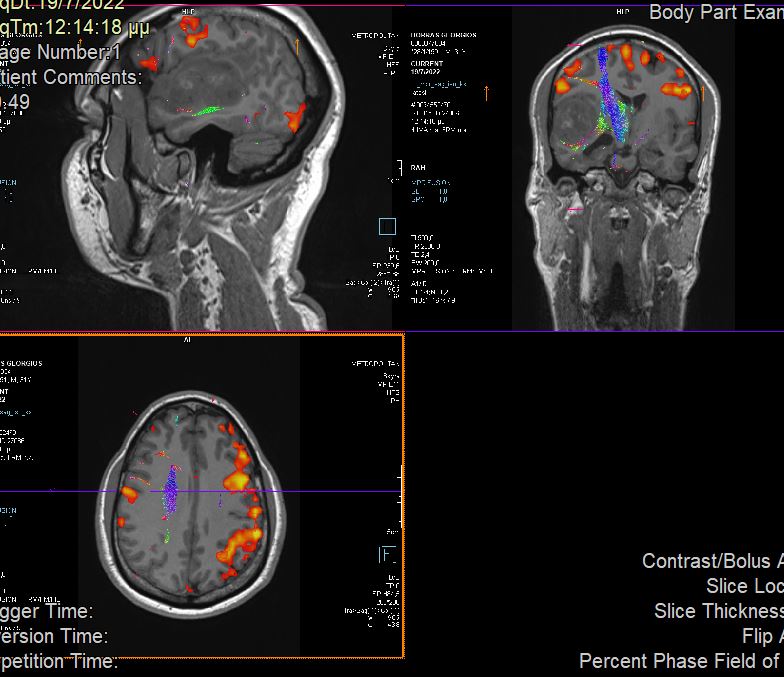

Χωροκατακτητική Εξεργασία δεξιού Κροταφικού Λοβού